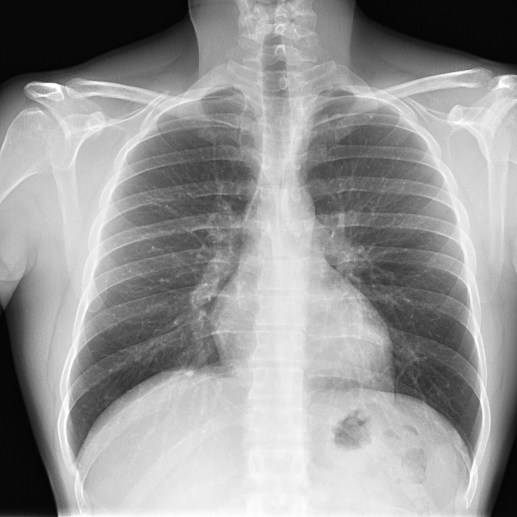

Empecemos, ¿qué ves?

- Comprobar que la placa está bien centrada e inspirada (6 arcos costales anteriores ó 9 posteriores).

- Abdomen y Diafragma

- Partes blandas y estructura ósea.

- Mediastino con silueta cardiaca.

- Parénquimas pulmonares (por separado)

- Comparar un pulmón con otro.

Seguir esta sistemática, dejando el pulmón para el final no nos olvidaremos de lo más importante.

Regla: Acaso Tiene Mucha Patología Pulmonar (Abdomen, Tejidos blandos y hueso, Mediastino, Pulmón por separado, Pulmón bilateral)

Nota: ¡¡¡No olvidar la placa lateral!!! La regla a seguir es la misma. Leer abdomen y diafragma, examinar parte posterior, tejidos blandos y subir por la columna; tráquea y descender por mediastino. Finalmente pulmones.

Solución: Es un estudio Normal. Silueta cardiomediastínica y parénquimas pulmonares sin alteraciones significativas.